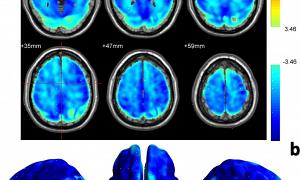

ד"ר לופרה מסביר שעם מחלת האלצהיימר, יש סוג של הצטברות של "זבל" במוח. הוא מורכב מחלבון הנקרא עמילואיד. שברים ממנו נדבקים זה לזה ויוצרים מעין "דבק" הנדבק לנוירונים וגורם למספר תקלות במוח. החלק השני של ה"זבל" הוא טאו, שעוטף את הנוירון, "נועל" אותו והורג אותו. טאו מזיק יותר.

לאחר מחקרים מדוקדקים בבוסטון, מומחים גילו שמוחו של החולה היה מלא בעמילואיד, אפילו יותר מאשר במקרים אחרים. עם זאת, היה לה מעט מאוד טאו. המחקר איפשר להם לאמת שבמטופל המסוים הזה, מוטציה נוספת עיכבה את ייצור הטאו וזה מה שעיכב את התקדמות המחלה.